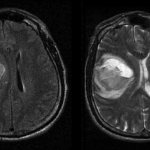

Помимо общефизических ощущений, защемление седалищного нерва необходимо подтвердить клинически. Прежде чем назначить терапию в городе Санкт-Петербург, мастер массажа должен определить характер защемления и точную зону. Для этого пациенту необходимо сделать рентген позвоночника, КТ, МРТ, ЭФИ нервно-мышечной системы. Помимо данных исследований, требуется сдать общий анализ крови, который покажет наличие воспалительных процессов в организме. Приступать к массажу можно только после того, как прошла острая воспалительная фаза и боль.

Чтобы подтвердить диагноз, определить причину болезни и определить состояние тканей, он направляет пациента на диагностику:

- рентгенографию;

- ультразвуковое исследование;

- денситометрию;

- компьютерную или магнитно-резонансную томографию;

- анализ крови на инфекции и аутоиммунные заболевания;

- анализ на онкомаркеры (при подозрении на наличие опухоли).